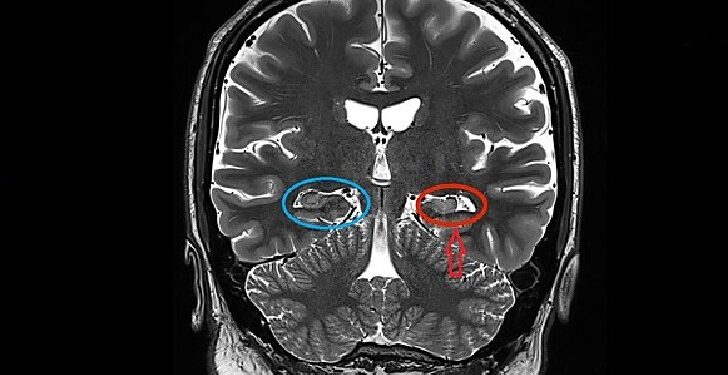

What causes multiple sclerosis symptoms?

Degeneration of the sheath that covers the neurons of the central system and the replacement of this sheath with scar tissue.